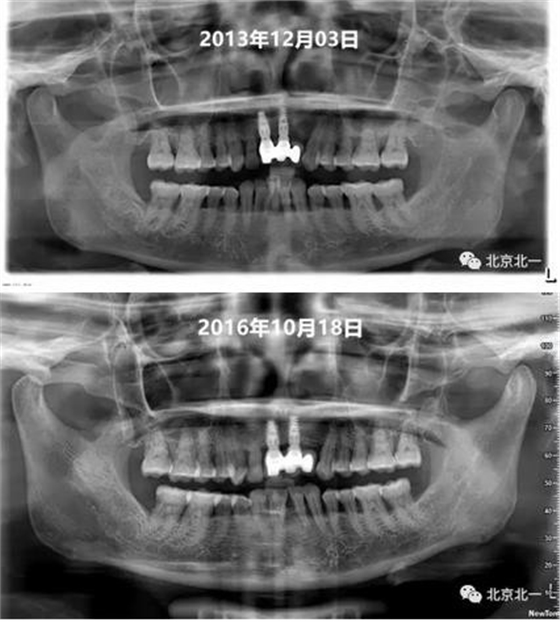

圖十、圖十一:2013年到2016年比較X片,骨平面很穩(wěn)定。牙齦及牙周黏膜健康,區(qū)別在于2016年時(shí)候31牙位缺失。

附:關(guān)注箭頭所示,診斷為結(jié)合牙還是融合牙?牙冠結(jié)合一起, 牙根分開。